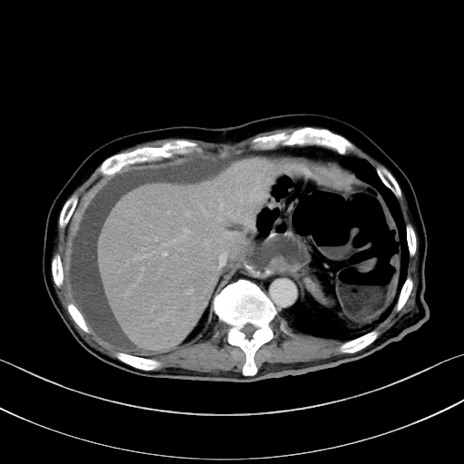

冠状断像

【症例】60歳代男性

【現病歴】胃癌にて胃全摘後。食思不振が悪化し、夜中に嘔吐することがある。

【既往歴】胃癌、胃全摘、脾摘、胆摘後

【データ】WBC 5900、CRP 10.56